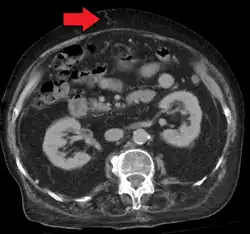

In addition, a widened (dilated) portal vein as seen on a CT scan or MRI may raise the suspicion about portal hypertension. A cutoff value of 13 mm is widely used in this regard, but the diameter is often larger than this is in normal individuals as well.[9]

A dilated portal vein (diameter of greater than 13 or 15 mm) is a sign of portal hypertension, with a sensitivity estimated at 12.5% or 40%.[18] On Doppler ultrasonography, a slow velocity of <16 cm/s in addition to dilatation in the main portal vein are diagnostic of portal hypertension.[19] Other signs of portal hypertension on ultrasound include a portal flow mean velocity of less than 12 cm/s, porto–systemic collateral veins (patent paraumbilical vein, spleno–renal collaterals and dilated left and short gastric veins), splenomegaly and signs of cirrhosis (including nodularity of the liver surface).[17]